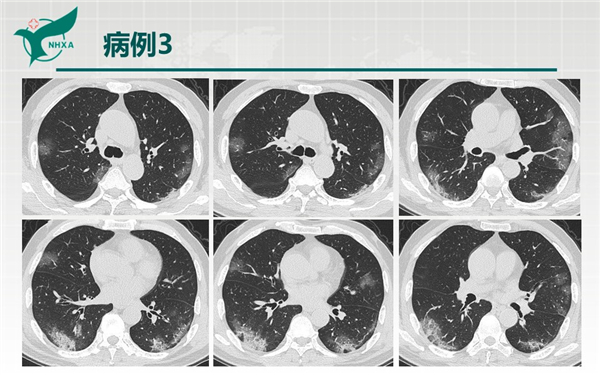

幻燈片10.jpg